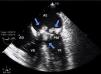

Exames laboratoriais com leucocitose discreta, sem eosinofilia. Ao ecocardiograma transtorácico foi evidenciada imagem sugestiva de vegetação em prótese valvar biológica, confirmada através do exame transesofágico (Figura I). Após coletas de hemoculturas, foi iniciado esquema antimicrobiano empírico. Paciente evoluiu com pioria do quadro infeccioso e instabilidade hemodinâmica. Com isso, foi submetido à troca da valva mitral biológica por prótese metálica. A vegetação aderida à prótese foi enviada para a cultura e, após sua análise macroscópica (Figura 2), foi sugerido associar Anfotericina B. No sexto dia de pós‐operatório houve o crescimento de Trichosporon beigelii na cultura da válvula e, como houve pioria clínica, o antifúngico foi trocado por Voriconazol. Contudo, o paciente evoluiu com falência de múltiplos órgãos, seguida de óbito no 13.° dia após a intervenção cirúrgica.